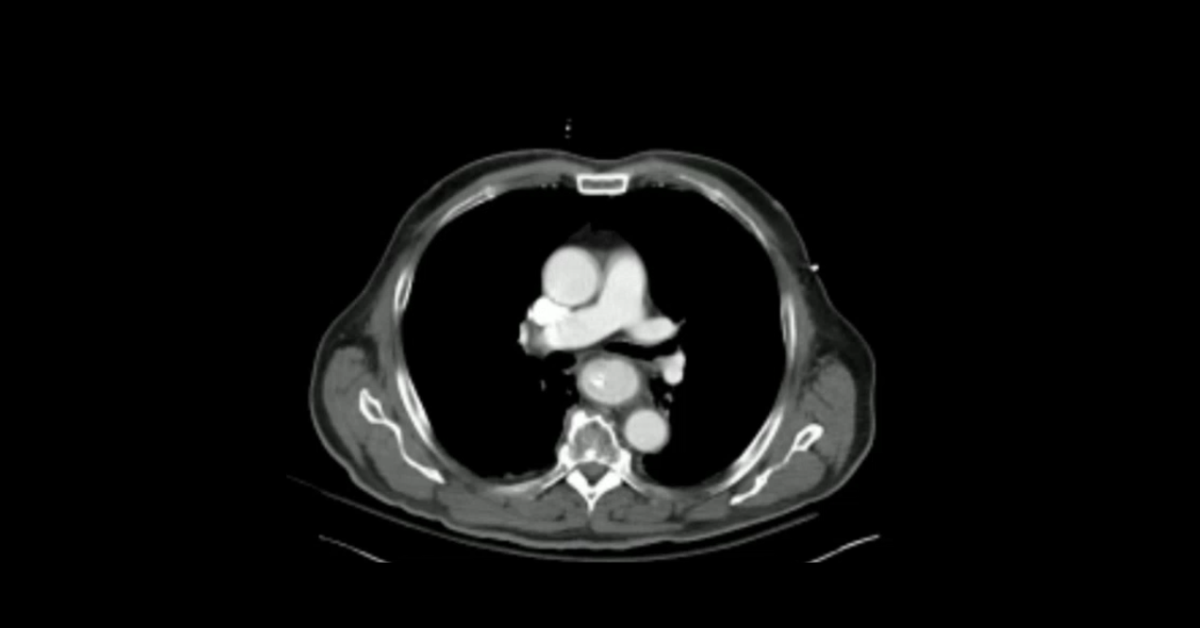

Cases of gastroesophageal pathology demonstrating a variety of perforations, fistulae, and volvulus.

1. Understand the different imaging appearances distinguishing abrupt from progressive esophageal ruptures.

2. Learn the appearance of esophageal fistulas to different mediastinal structures.